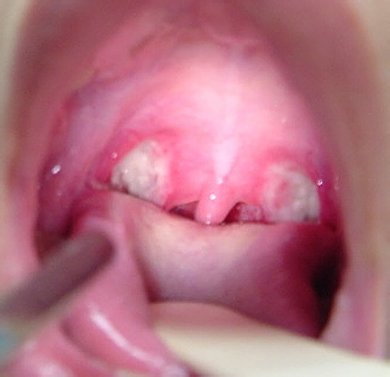

Симптомы тонзиллита у женщин во время вынашивания ребенка, в целом, не отличаются от традиционных признаков заболевания, и включают:

- боль в горле;

- ощущение кома или инородного предмета;

- першение и частый сухой кашель;

- общее недомогание;

- повышение температуры тела.